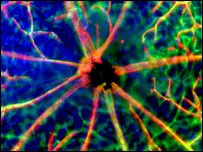

| The cells grow along silk fibres

A picture of nerve cells growing on the silk is one of the winning images in this year's Wellcome Trust Biomedical Image Awards.

The team has tested the silk in tissue culture (shown in the winning image) and in animals - and in both cases, said Professor Priestly, the results had been good.

He added: "The picture shows two things: reddish coloured processors, which are the nerve fibres growing along the silk; and blue supporting cells, called Schwann cells, which are very important in supporting nerve regeneration. "And in animal studies we have shown, both in the spinal cord and in peripheral nerves, the silk fibres support nerve growth."